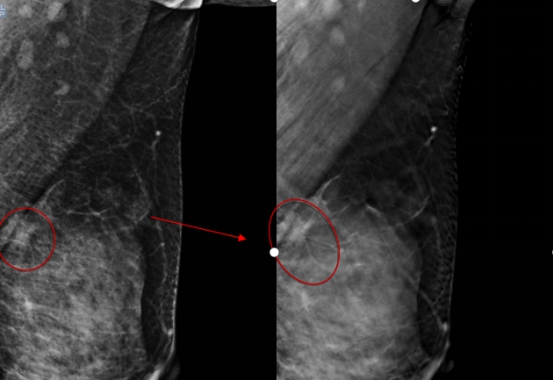

ac米兰官网中文网站一院放射科主任陈颖教授介绍,由于李女士比较年轻,属于致密型乳腺,常规的乳腺钼靶摄片未发现明显的肿块,仅显示双乳增生及良性钙化。数字化乳腺断层摄影断层图像显示左乳外上象限长了一个5mm的结节,经放射线科钼靶室医生会诊发现,该结节有很大可能性是恶性的乳腺癌,因此建议李女士做活检或者入院手术治疗。术中冰冻切片发现该结节是乳腺原位癌,因此医生为她制定了保乳手术的治疗方案,目前正在康复中。术后,李女士特意打电话感谢放射线科的医生们帮助她及早地发现了这个病灶。

2020年末ac米兰官网中文网站一院放射线科引进(HOLOGIC)数字化断层乳腺机,与传统的数字化钼靶乳腺机相比,能够最大限度地减少乳腺组织重叠,尤其是对年轻东方女性的致密型乳腺能够明显提高病灶检出率,大大降低了假阳性率及假阴性率。